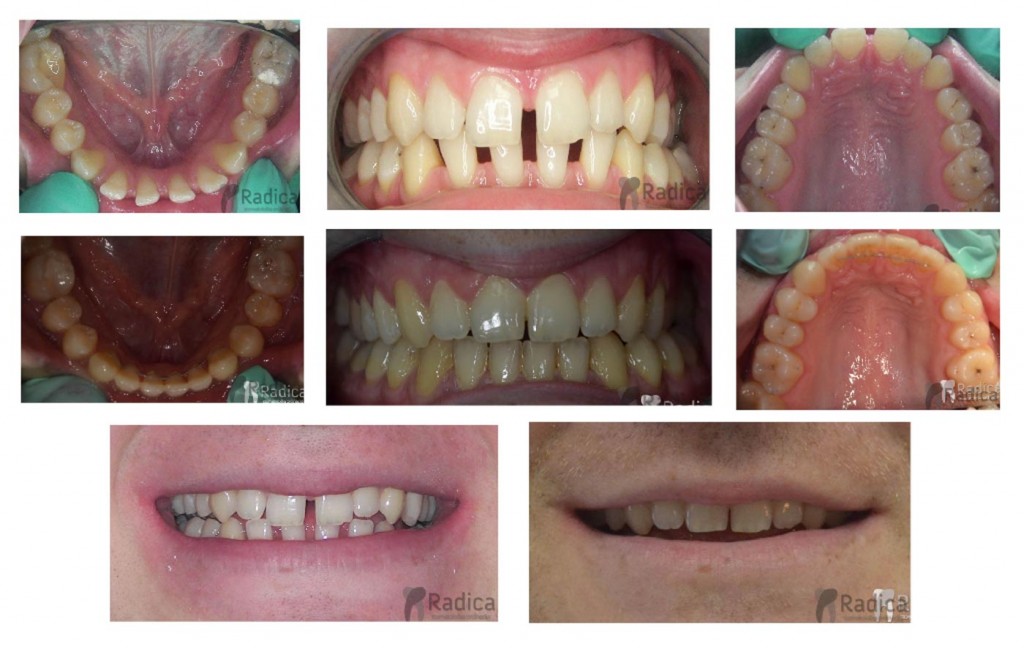

U sljedećem primjeru prikazan je pacijent s progenijom i hypodontiom (nedostatkom) oba gornja lateralna sjekutića. Ortodontskom terapijom je dobiven normalan pregriz i prostor za nadoknadu lateralnih sjekutića. Radi estetskih razloga u toku terapije su dodana dva zuba koja nedostaje. Nakon završene ortodontske terapije pacijent je upućen svom stomatologu koji mu je napravio protetski rad.